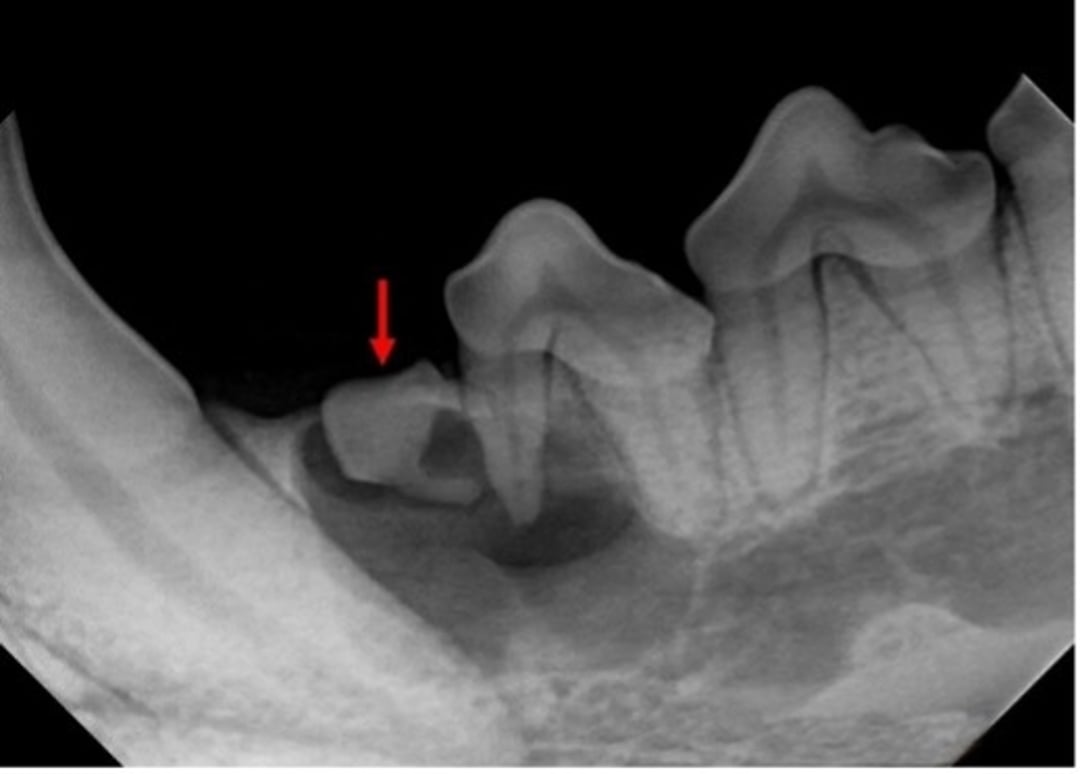

Primer premolar mandibular izquierdo no erupcionado (flecha roja) de un perro. Nótese el área radiotransparente que rodea el diente no erupcionado justo distal al canino. Además, el área quística parece afectar al segundo premolar mandibular izquierdo. Una lesión quística asociada con un diente no erupcionado es coherente con un quiste dentígero.

Cortesía de la Dra. Brenda Mulherin.